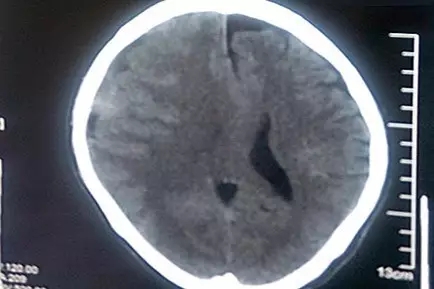

患者术前CT影像:脑中线结构向左偏移

老冯才告诉了家人。县医院CT诊断结果比他想象的严重得多!这大树枝把他砸出了亚急性硬脑膜下血肿,出血量较大,脑中线已经移位,并有脑疝风险。马不停蹄的老冯一家到了省城的三甲医院,接着又赶到了上海的三甲医院,然而都以各种理由被建议转院治疗。不幸中的万幸是,老冯的亚急性硬脑膜下出血相比急性硬脑膜下出血,出血速度稍缓,所以血肿形成至脑受压的过程略长,为老冯四处求医争取了宝贵的时机。